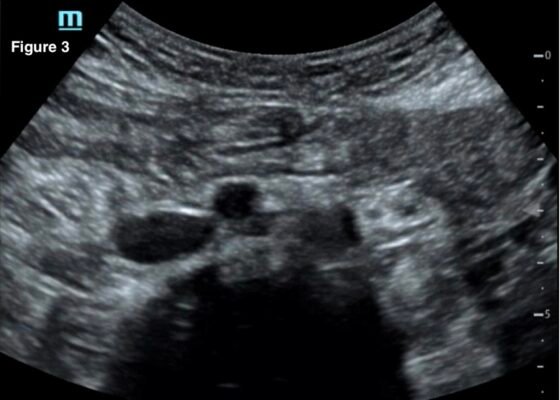

DOI: https://doi.org/10.21980/J82W7TA transabdominal point-of-care ultrasound (POCUS) was initiated to determine whether an abnormality to the pregnancy could be identified. Curvilinear probe was used. Our transabdominal POCUS, in the transverse plane, showed a heterogenous mass with multiple anechoic areas in the uterus. The white arrow on the ultrasound identifies these findings. The classic “snowstorm” appearance was concerning for molar pregnancy.